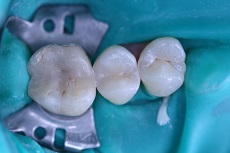

![]() |

Foto 21, 22: Ukázka odstranění kosmetického defektu, a to nevzhledné výplně, která byla stomatoložkou vyměněna za estetickou, bílou.

Foto 23, 24: Ukázka estetické opravy – sanace chrupu.

Foto 32-34: Ukázka výplně a jejího provedení estetickou stomatoložkou, vlevo stav před (podkažená výplň kvůli nedodržení vhodného postupu pro práci s kompozitním materiálem) uprostřed v průběhu ošetření a vpravo stav po ošetření).